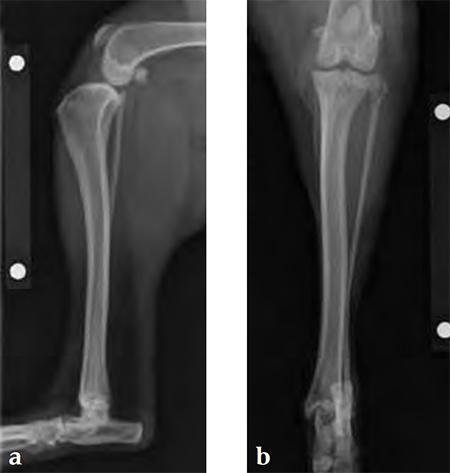

A 4-year-old, female, spayed, 33 kg English bulldog had a CrCL tear and a medial patellar luxation. The small stature 3.5 mm TPLO plate was perfect for this dog due to the small profile of the bone and the need to use a heavier plate (3.5 vs a 2.7 mm). In the past, veterinary surgeons have been forced to either squeeze the standard TPLO 3.5 mm plate on the bone or use an undersized TPLO 2.7 mm plate. In this patient, the shorter and smaller profile head of the small stature TPLO 3.5 mm was perfect.